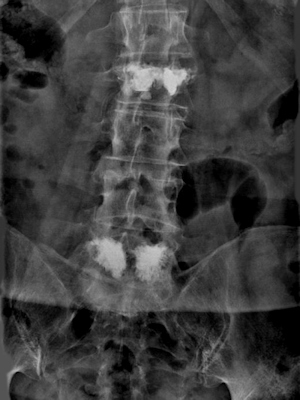

my spine: two vertebrae, fractured by a fall, have required spinal surgery.

Rückgrat

my spine:  two repairs

in March 2025